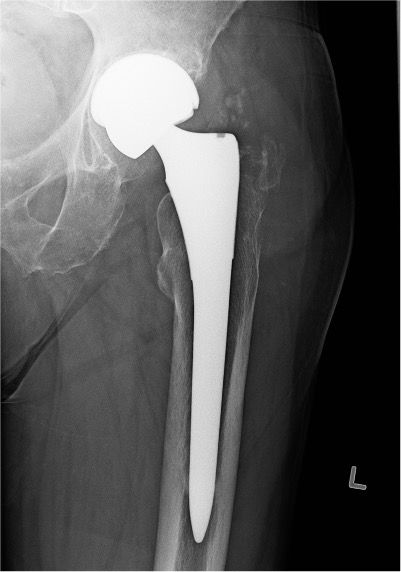

Metal on Metal

Advantage

Large heads

- 30 - 60 mm

- decreases dislocation

- ?improves ROM / function

Disadvantages

1. Increased ion levels

Cobalt and Chromium ions elevated in blood

Creatine cobalt and Creatinine chromium elevated in urine

2. Adverse Local Tissue Reactions

3. High revision rates / Prosthesis recall / Class actions